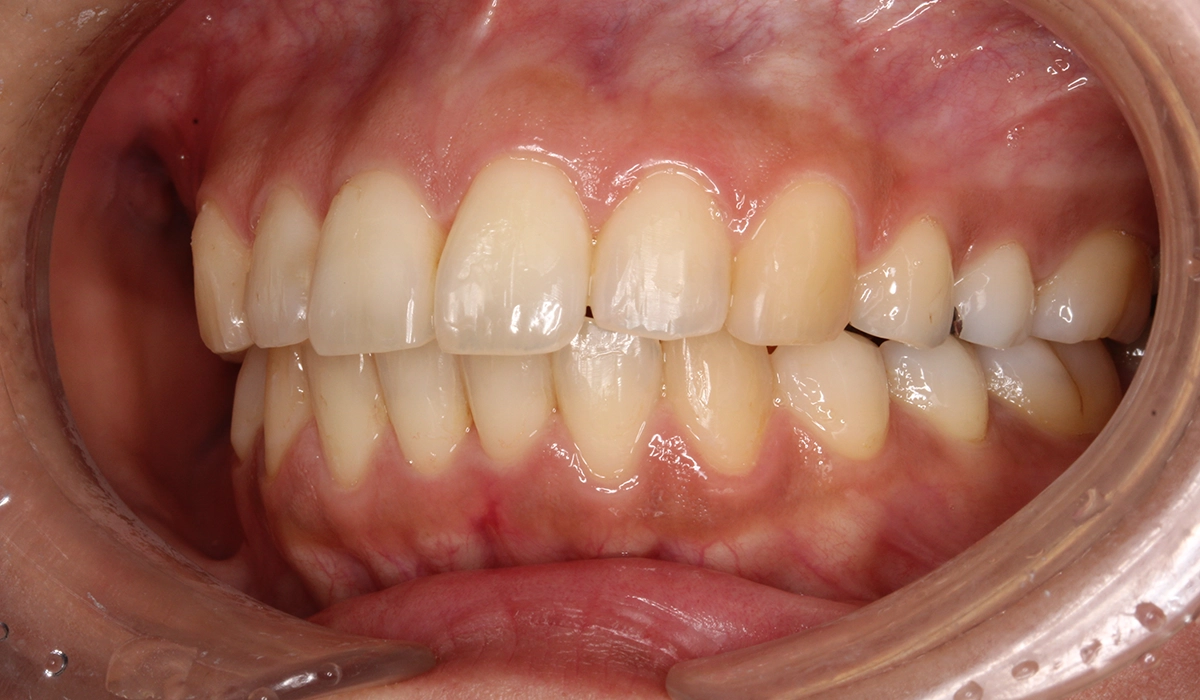

術前:正面

術後:正面